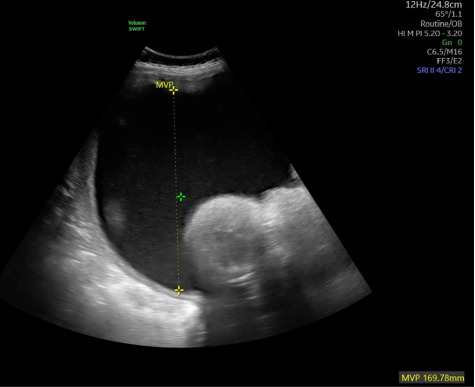

Nonimmune hydrops fetalis (NIHF) refers to the pathologic accumulation of fluid within the fetus due to causes other than red cell alloimmunization and now accounts for up to 90% of fetal hydrops cases. Fetal hydrops is associated with significant morbidity and mortality, and the exact prognosis is largely dependent on the underlying etiology. The most common etiologies include cardiovascular causes and chromosomal or genetic abnormalities. Despite this, diagnostic testing with karyotype or chromosomal microarray only identifies approximately 25% of cases, and up to 20% of cases remain idiopathic or unknown. We report the first known case of NIHF related to a NOTCH1 pathogenic variant. In this case, NIHF was diagnosed at 30 weeks' gestation in a fetus with low-risk prenatal genetic screening, noncontributory anatomic survey, and normal chromosomal microarray. The hydrops was uniquely localized to scalp edema and pleural effusions requiring bilateral thoracentesis and never progressed to involve pericardial effusion or ascites. Whole exome sequencing diagnosed a novel pathogenic variant in the NOTCH1 gene. This is the first reported case of NIHF in the setting of NOTCH1 pathogenic variant and is an important addition to the existing literature on this incredibly diverse, high-risk pathology.

Abstract Image